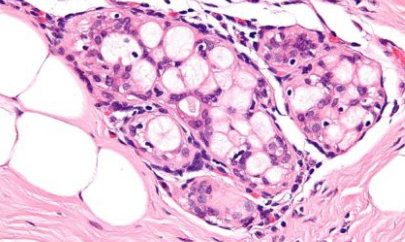

人工智能已经被用于诊断癌症并跟踪其进展。现在,科学家们开发了一种工具,可以用ERBB2(促进癌细胞生长的癌蛋白)检测乳腺癌病例的典型肿瘤形态特征。这项技术的实用性非常明显——ERBB2蛋白过度表达的患者可以从针对ERBB2受体的单克隆抗体治疗中受益。正确识别它们可以导致更明智的治疗选择和更好的结果。

芬兰的科学家表明,人工智能算法可以直接从肿瘤形态学中学习预测肿瘤ERBB2状态的模式。该研究的作者之一德米特里·比奇科夫(DmitriiBychkov)解释说:“我们的结果表明,肿瘤的形态特征包含有关疾病生物学的大量信息,可以通过机器学习方法提取。这些有价值的数据可以帮助临床决策”。研究人员用来自乳腺癌患者的真实组织样本进行了测试,发现人工智能非常擅长确定哪些患者更有可能获得更有利的疾病结果。这将非常有助于做出与治疗方案相关的选择。